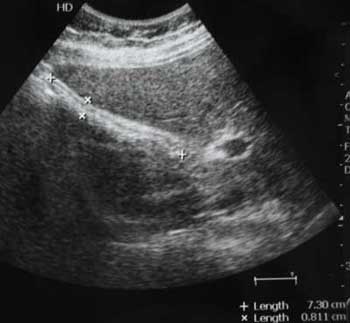

Молодой мужчина с болями в эпигастральной области.

Осматривался дважды натощак. Выявлены изменения желчного пузыря.

Печень, селезенка при УЗИ не изменены.

Прошу помочь с заключением.

Запустевший желчный пузырь болей не даёт. При верхнеабдоминальном синдроме необходимо также проводить ФГДС.

Если этот желчный пузырь не удается "вытянуть", то он не сократившийся, а нефункционирующий ИМХО.

Думаю,что это не просто пустой ж.пузырь,он содержит гиперэхогенное включение в середине,повторяющее форму ж.пузыря и дающее позадиакустическую тень.Возможна кальцифицированная аскарида :)

Нефункционирующий желчный пузырь содержит гиперэхогенное включение.

Первый ж.пузырь удален, клинический диагноз "сморщенный желчный пузырь, ЖКБ", гистология - фиброз стенок желчного пузыря.